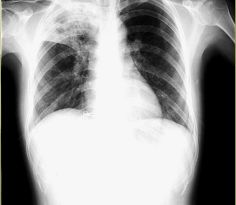

胸部X線檢查病初可見沿肺門向周邊走向的炎症浸潤,以後出現散在性片狀、絮狀影,常分布於多個肺野,晚期則呈融合改變,多集中於肺野的內中帶,類似肺水腫。